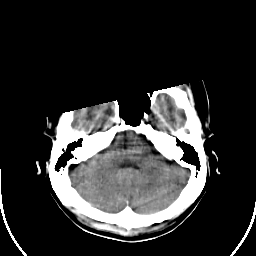

Sarcoma: Roentgen-ray CT -- Slice #5

[Home][Help][Clinical] Slice 5